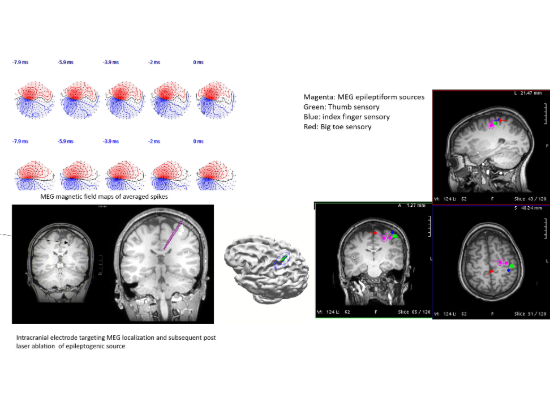

meg article 2One significant implementation of the MEG is for use in epilepsy surgery to determine where in the brain seizures originate. Surgeons can use the results of a MEG scan to plan epilepsy surgeries.

“When we’re doing epilepsy surgery and trying to figure out if patients are a surgery candidate, we need to know exactly where the seizures are coming from as precisely as possible, and many times we end up putting electrodes in the brain to sample that activity directly,” Cox said. “So having studies like MEG, where we can have a precise idea of where to put those electrodes, is very helpful.”

Kristen Riley, M.D., professor in the UAB Department of Neurosurgery, notes that “MEG studies help us as surgeons to localize seizure onset zones, directing us to areas to implant monitoring electrodes. Often these areas look completely normal on MRI, but are identified by the MEG study as possible sites of seizure onset.”

A second clinical implementation involves functional brain mapping—to localize areas important for language, sensory and motor function.